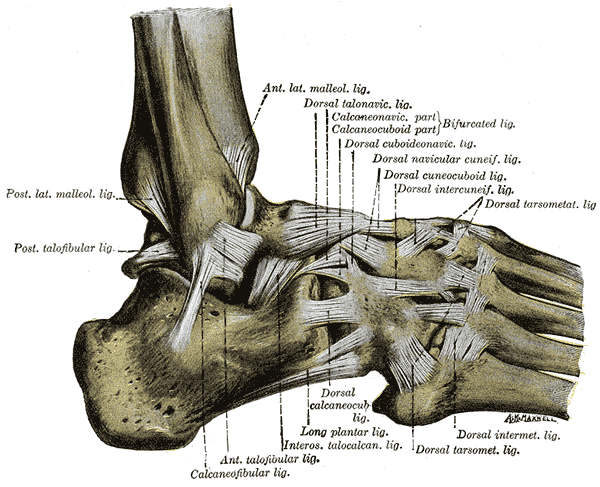

Lad os først og fremmest tale lidt om anatomi. Ankelleddet består af to forskellige led:

- Talocrural-leddet , som er et hængselled, der tillader de to primære bevægelser i sagittalplanet: plantarfleksion og dorsifleksion.

- Subtalarleddet betragtes også som et hængselled, men dets rotationsakse løber skråt. De mulige bevægelser i dette led er: inversion (en kombination af plantarfleksion, adduktion og supination) og eversion (en kombination af dorsifleksion, abduktion og pronation).

Bemærk: I den amerikanske nomenklatur kaldes inversion for supination og eversion for pronation.